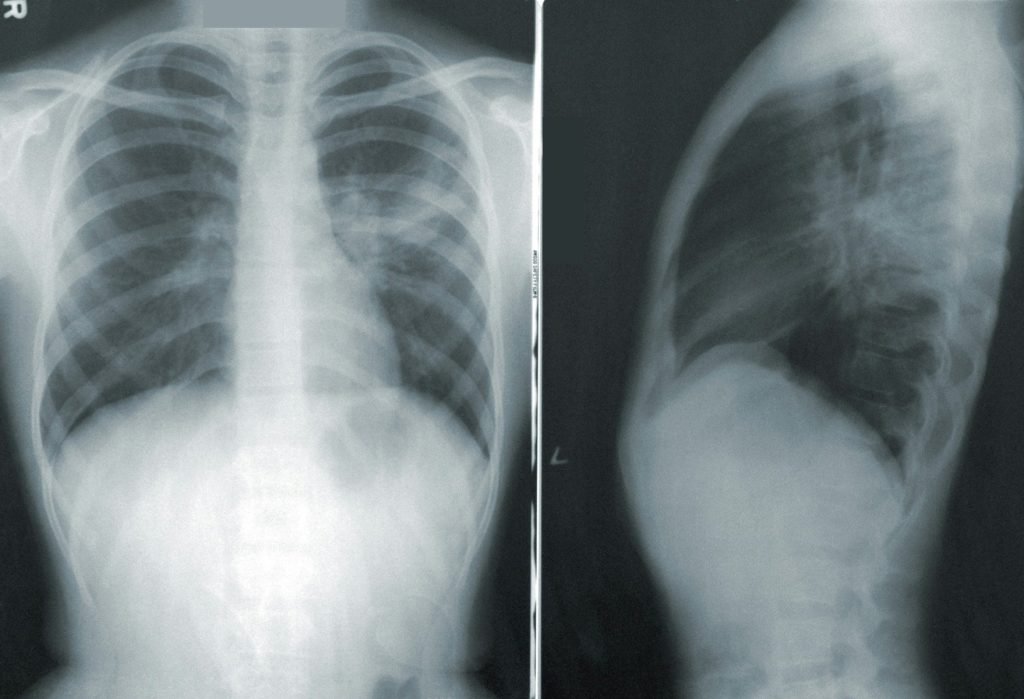

Tuberculoza este o boală tratabilă și prevenibilă, cauzată de o bacterie care afectează cel mai adesea plămânii. Se transmite pe cale aeriană, atunci când persoanele infectate tușesc, strănută sau scuipă.